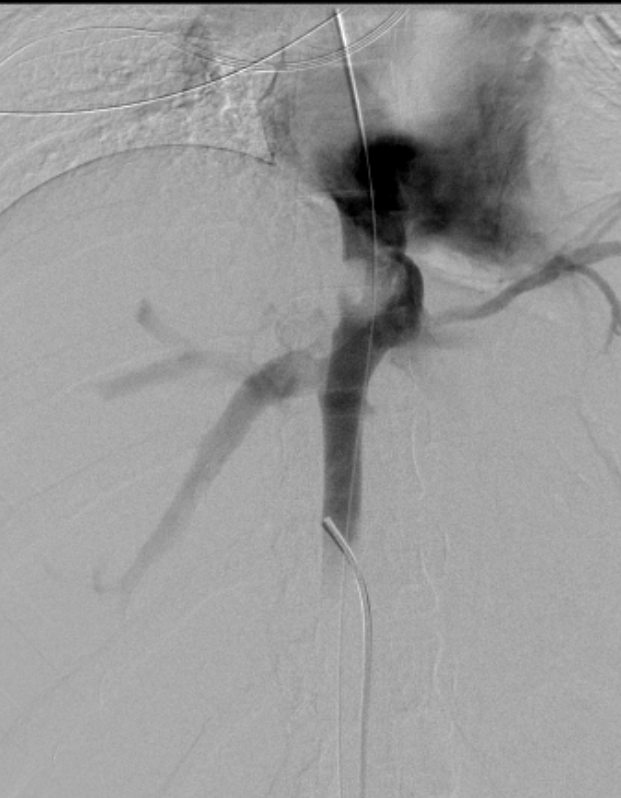

Estenosis vena cava inferior